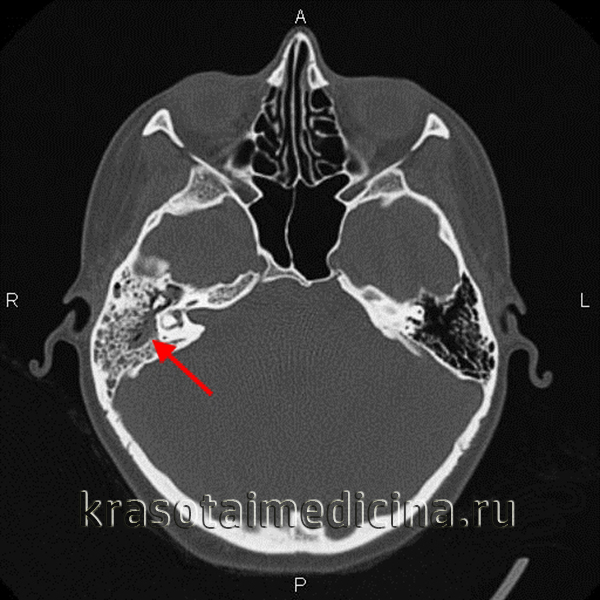

а Затемнение барабанной полости и сосцевидного отростка слева при хроническом среднем отите.

КТ: начальные признаки эрозии костей и деструкция слуховых косточек.

b, с Хронический средний в отит и холестеатома правого уха у женщины 43 лет. КТ, горизонтальная проекция: в заполнение барабанной полости измененными в результате хронического воспаления тканями и эрозирование крыши барабанной полости. Эрозирование кости более четко выявляется во фронтальной плоскости.